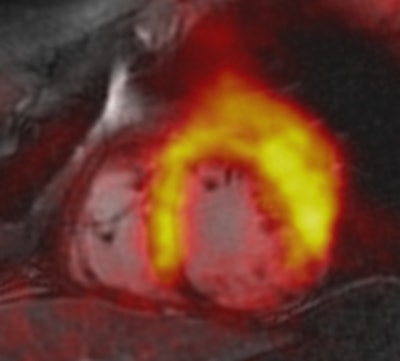

The MRI protocol included a two-point Dixon sequence for attenuation correction, cine imaging, and late gadolinium enhancement imaging. PET scans were performed with FDG and acquisitions were electrocardiogram (ECG)-gated in one bed position with 3D image reconstruction. Visual assessment was based on coregistered short-axis slices using a 17-segment model from the American Heart Association.

Tracer accumulation in each myocardial segment was compared with regional wall motion abnormalities and with signal intensity in late gadolinium-enhanced images. The size of the infarction zone was measured on both late gadolinium-enhanced and FDG-PET images.

There was good agreement between PET and late gadolinium enhancement and PET and cine imaging, the researchers found. With PET, 31% of the myocardial segments showed a decrease in FDG tracer uptake, indicating an infarcted area. With late gadolinium enhancement, 28% of the infarcted myocardial segments were visible, and 24% of the segments showed abnormal wall motion with cine imaging.

To better evaluate the quantitative imaging results, Nensa and colleagues developed in-house software to generate coregistered images, which compared late gadolinium-enhanced images with results from FDG-PET. Using the software in a separate group of 15 patients with visually conclusive agreement between PET and late gadolinium enhancement results, the researchers found PET defect size (35 mL) to be significantly larger than the late gadolinium-enhanced defect size (27 mL).